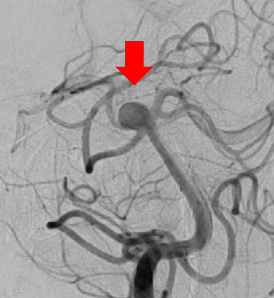

脳動脈瘤

動脈瘤の中に入っているコイル

治療後コイルによって動脈瘤が見えなくなっています